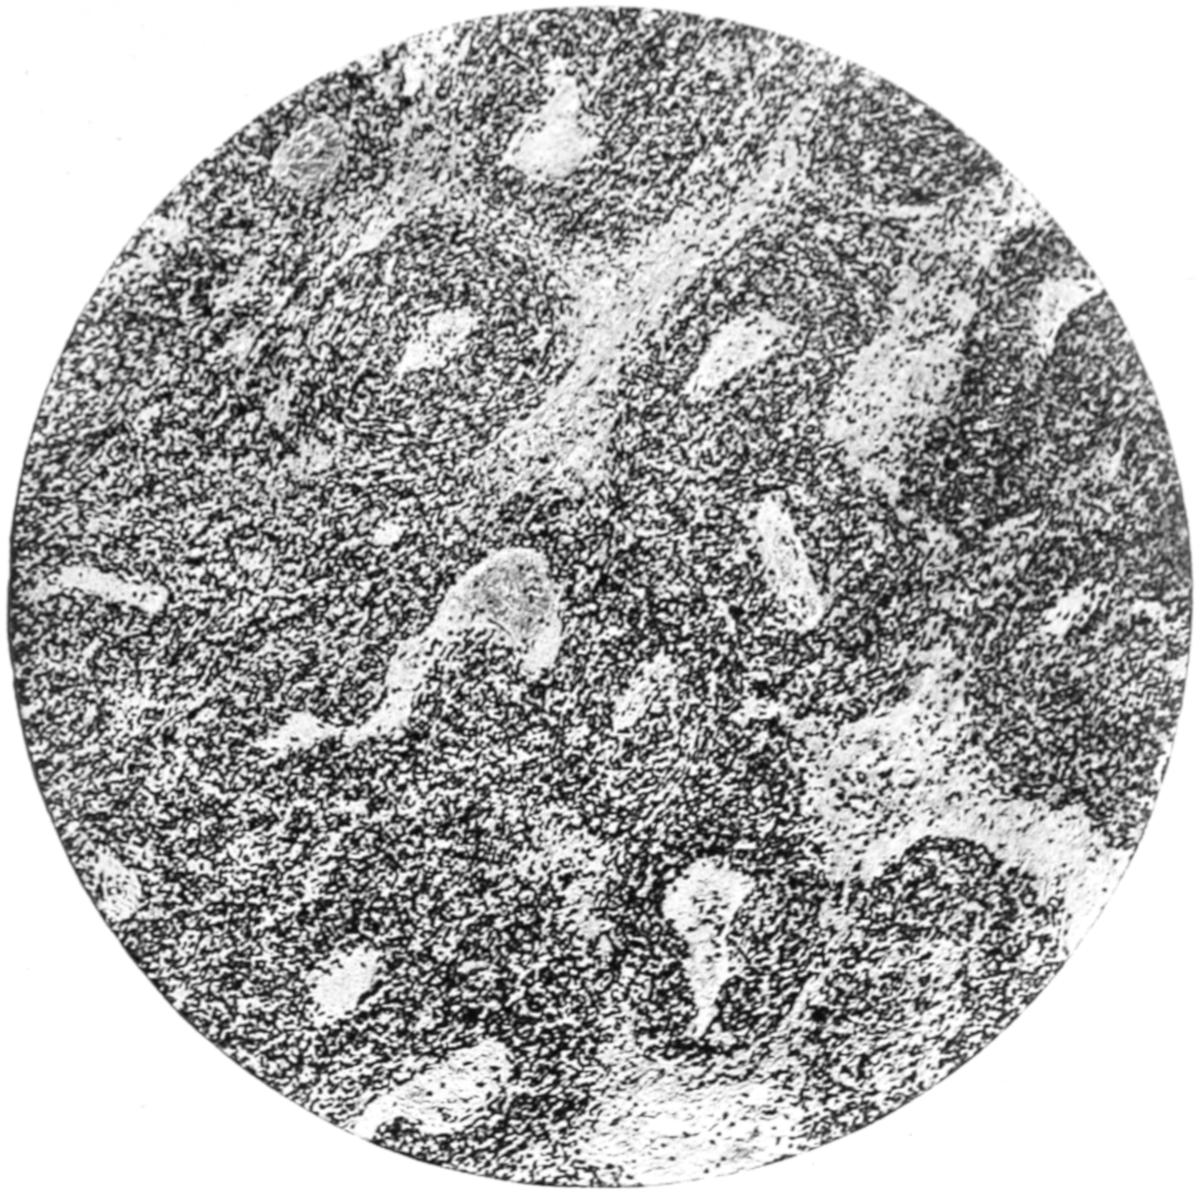

PLATE I

Fig. I.

Fig. II.

Fig. III.

Fig. IV.

Fig. V.

Fig. VI.

Fig. VII.

Fig. VIII.

DRAWN BY J. N. Z. CHASE

PLATE I.

BLOOD.

(Ehrlich triple stain.)

(Prepared by Dr. I. P. Lyon.)

Fig. I. TYPES OF LEUCOCYTES.

a. Polymorphonuclear Neutrophile. b. Polymorphonuclear Eosinophile. c. Myelocyte (Neutrophilic). d. Eosinophilic Myelocyte. e. Large Lymphocyte (large Mononuclear). f. Small Lymphocyte (small Mononuclear).

Fig. II. NORMAL BLOOD.

Field contains one neutrophile. Reds are normal.

Fig. III. ANÆMIA, POST-OPERATIVE (secondary).

The reds are fewer than normal, and are deficient in hæmoglobin and somewhat irregular in form. One normoblast is seen in the field, and two neutrophiles and one small lymphocyte, showing a marked post-hæmorrhagic anæmia, with leucocytosis.

Fig. IV. LEUCOCYTOSIS, INFLAMMATORY.

The reds are normal. A marked leucocytosis is shown, with five neutrophiles and one small lymphocyte. This illustration may also serve the purpose of showing the leucocytosis of malignant tumor.

Fig. V. TRICHINOSIS.

A marked leucocytosis is shown, consisting of an eosinophilia.

Fig. VI. LYMPHATIC LEUKÆMIA.

Slight anæmia. A large relative and absolute increase of the lymphocytes (chiefly the small lymphocytes) is shown.

Fig. VII. SPLENO-MYELOGENOUS LEUKÆMIA.

The reds show a secondary anæmia. Two normoblasts are shown. The leucocytosis is massive. Twenty leucocytes are shown, consisting of nine neutrophiles, seven myelocytes, two small lymphocytes, one eosinophile (polymorphonuclear) and one eosinophilic myelocyte. Note the polymorphous condition of the leucocytes, i. e., their variations from the typical in size and form.

Fig. VIII. VARIETIES OF RED CORPUSCLES.

a. Normal Red Corpuscle (normocyte). b, c. Anæmic Red Corpuscles. d-g. Poikilocytes. h. Microcyte. i. Megalocyte. j-n. Nucleated Red Corpuscles. j, k. Normoblasts. l. Microblast. m, n. Megaloblasts.

The value of a careful blood examination is well illustrated by Plate I, prepared by Dr. Irving P. Lyon, in which are displayed the alterations of greatest interest to the surgeon.